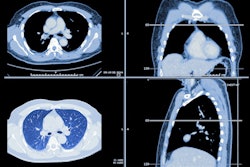

Lung cancer is the leading cause of cancer death in the U.S. and the second most common cancer diagnosed annually, according to the American Cancer Society. The USPSTF currently recommends annual screening with low-dose CT in adults aged 50 to 80 years old who have a 20-pack-a-year smoking history and currently smoke or have quit within the past 15 years.